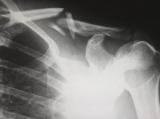

В медицинский центр «Наири» обратился мужчина 1951 года рождения с двусторонним анкилозирующим коксартрозом и ожирением первой степени. Пациент жаловался на боли, носящие постоянный характер...